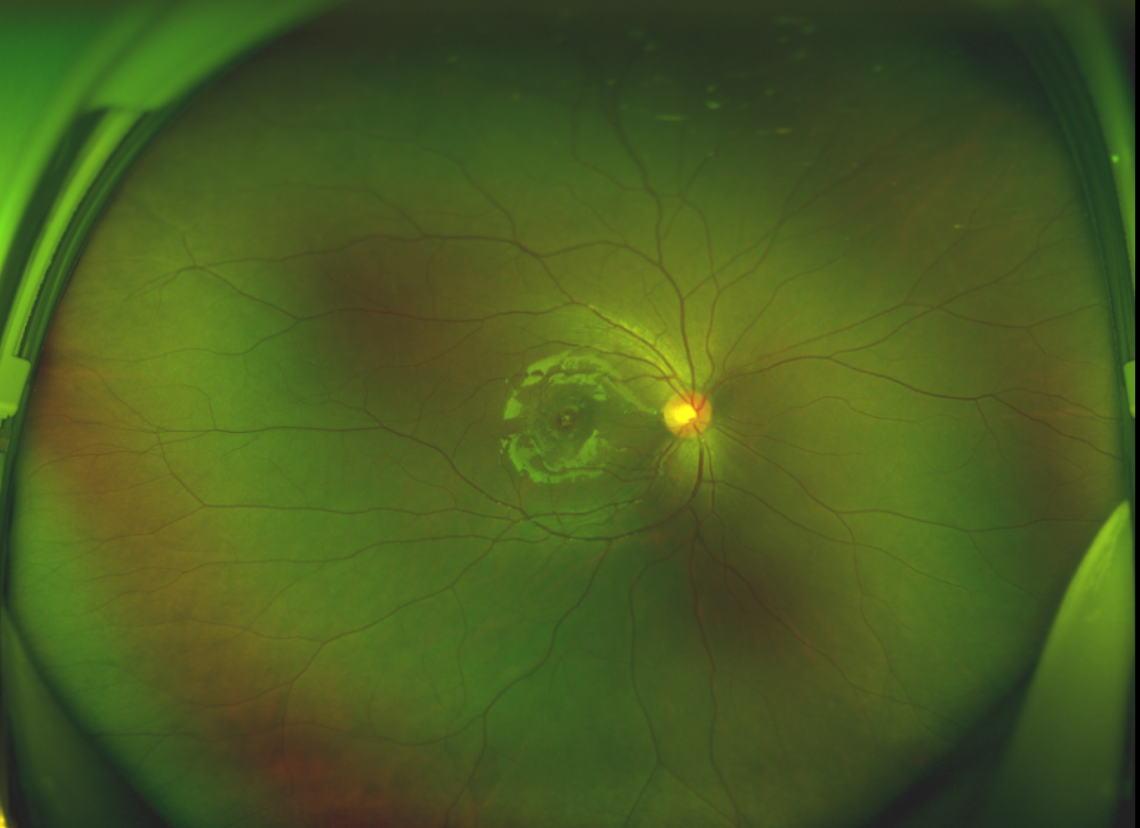

黃斑位于視網(wǎng)膜正中心,是視覺(jué)最敏銳的區(qū)域,堪稱“眼底的心臟”,負(fù)責(zé)我們閱讀、駕駛、識(shí)別人臉等精細(xì)視覺(jué)。 當(dāng)黃斑區(qū)的神經(jīng)組織出現(xiàn)全層缺損,形成一個(gè)“孔洞”,即為黃斑裂孔,它會(huì)直接導(dǎo)致中心視力急劇下降、視物變形、視野中心出現(xiàn)暗區(qū)。

經(jīng)過(guò)詳細(xì)的檢查和評(píng)估,王曉波主任決定采用“內(nèi)界膜翻轉(zhuǎn)覆蓋聯(lián)合粘彈劑固定術(shù)”為誠(chéng)誠(chéng)進(jìn)行治療。

術(shù)中,醫(yī)生精細(xì)剝離黃斑區(qū)的內(nèi)界膜后,并非直接丟棄,而是巧妙地給它翻個(gè)面,讓它變成一塊天然“創(chuàng)可貼”,嚴(yán)密覆蓋在黃斑裂孔的表面。覆蓋的內(nèi)界膜像微型支架一樣撐住裂孔邊緣,防止它擴(kuò)大;同時(shí),這層膜本身含有能促進(jìn)生長(zhǎng)的“養(yǎng)分”,能顯著刺激裂孔周圍的視網(wǎng)膜組織像爬山虎一樣快速生長(zhǎng)、蔓延過(guò)來(lái),最終把裂孔“補(bǔ)”好。

除此之外,利用自體組織覆蓋為黃斑裂孔提供了理想的愈合環(huán)境,裂孔閉合速度顯著快于傳統(tǒng)方法。誠(chéng)誠(chéng)接受手術(shù)24小時(shí)后,檢查可見(jiàn)內(nèi)界膜瓣位置良好;術(shù)后1個(gè)月,黃斑裂孔已經(jīng)閉合,視力恢復(fù)到0.5;術(shù)后兩個(gè)月,視力進(jìn)一步提升到0.7。